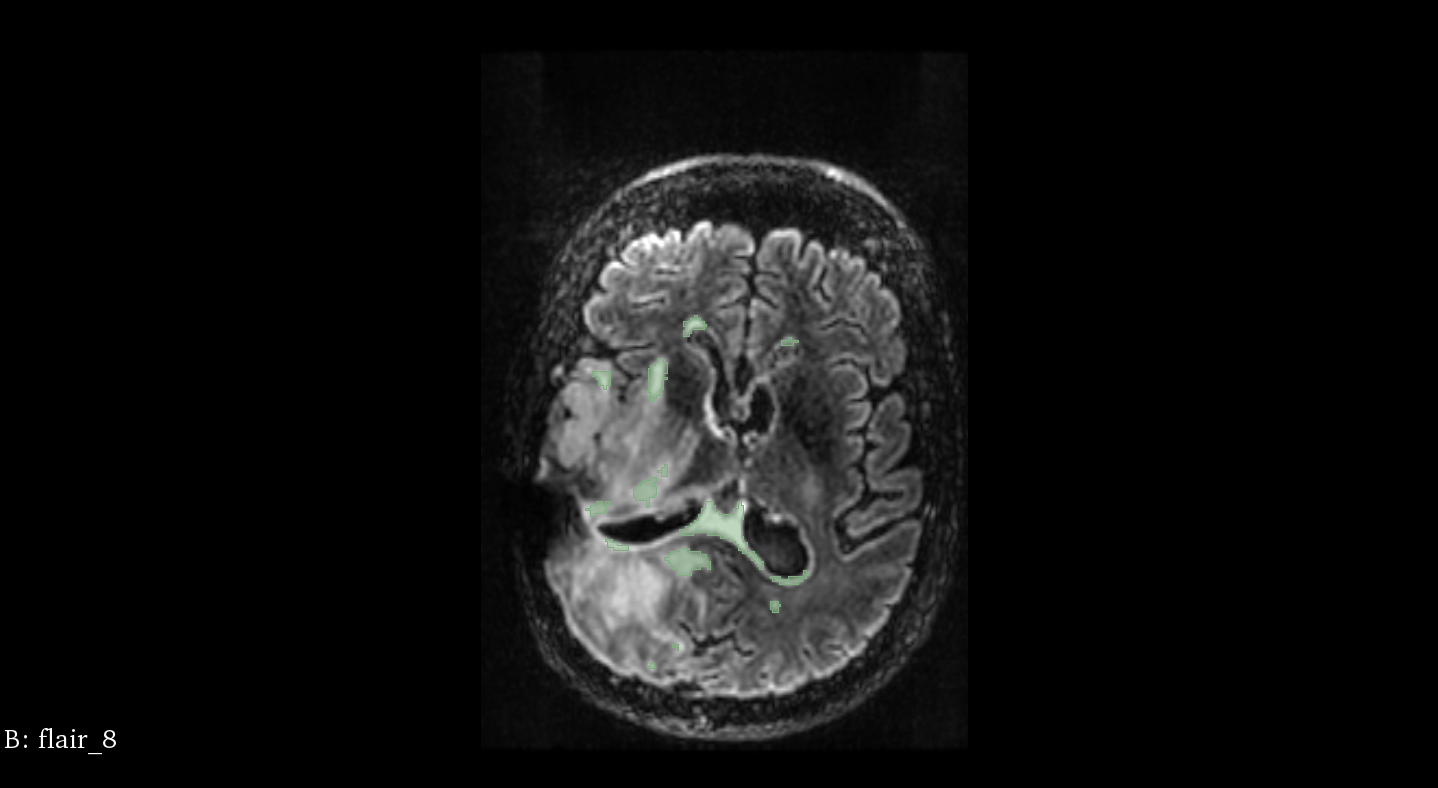

Patient 58

t=

9